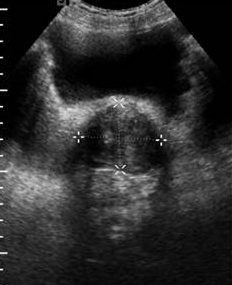

Estudio de Próstata con vejiga llena.

En la imagen anterior vemos la vejiga con líquido y una estructura posterior, hipoecogénica y que está medida, la próstata, que de no ser porque la vejiga está llena de líquido, no se podría haber estudiado tan bien.